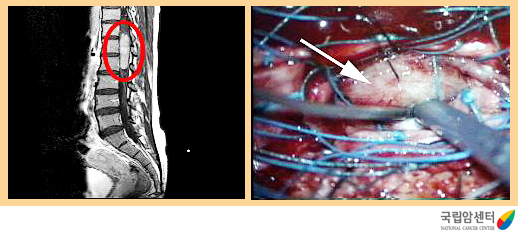

[ 척수종양의 자기공명영상촬영(MRI) 및 척수종양 수술 장면 ]

일차적 목적은 척수와 신경근의 기능을 회복하는 것입니다. 양성 비침윤성 종양 및 원발성 척수종양의 경우에는 근치를 목표로 하여 수술로 완전 제거하는 것이 최상의 치료방법이고, 악성종양이나 침윤성 종양의 경우에는 일시적인 신경 증상의 호전 또는 증상의 악화를 방지하는데 목표를 두어야 합니다. 수술 현미경과 초음파진단장비 등의 미세 신경 수술기법과 각각의 신경이 지배하는 피부 영역에 전기 신호를 감지 할 수 있는 전기생리학적 감시장치를 이용하면 척수내에 발생된 종양이라도 종양이 침범한 신경을 보호할 수 있어 신경학적 후유증 없이 완전 제거가 가능한 경우가 많습니다.

전이성 척추종양처럼 악성종양의 경우 척추체를 파괴하여 척추골절이 발생하기도 하므로 이런 경우는 기구를 이용한 척추 고정술이 필요하기도 합니다.